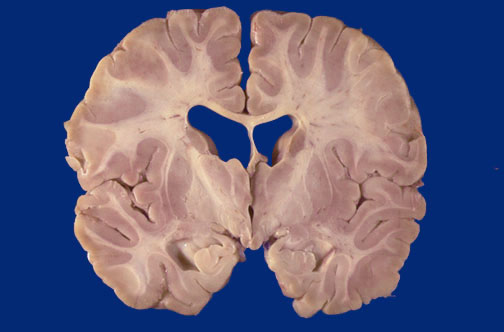

Identify the following regions of the normal brain by clicking in the image below:

Body of Caudate - Anterior Nucleus of Thalamus - Insular Cortex - Mammillary Bodies - Hippocampus - Mammillothalamic Tract